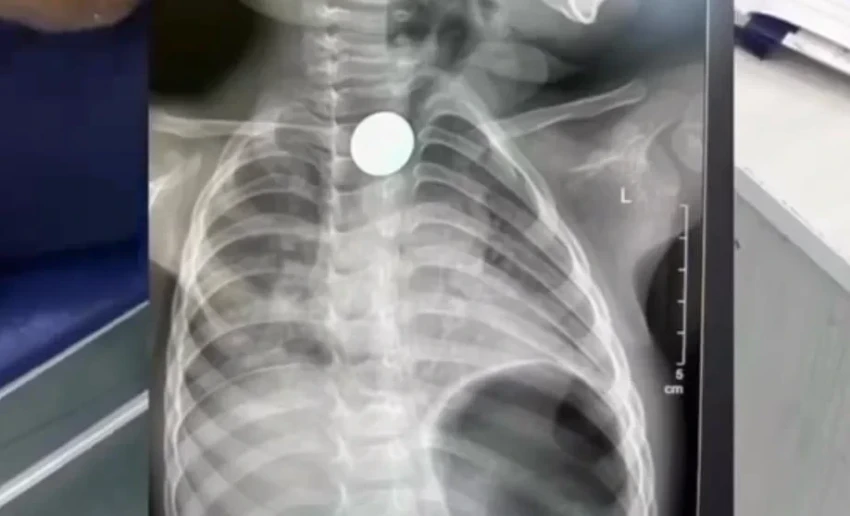

В Бишкеке врачи без операции извлекли монету из пищевода двухлетнего ребенка